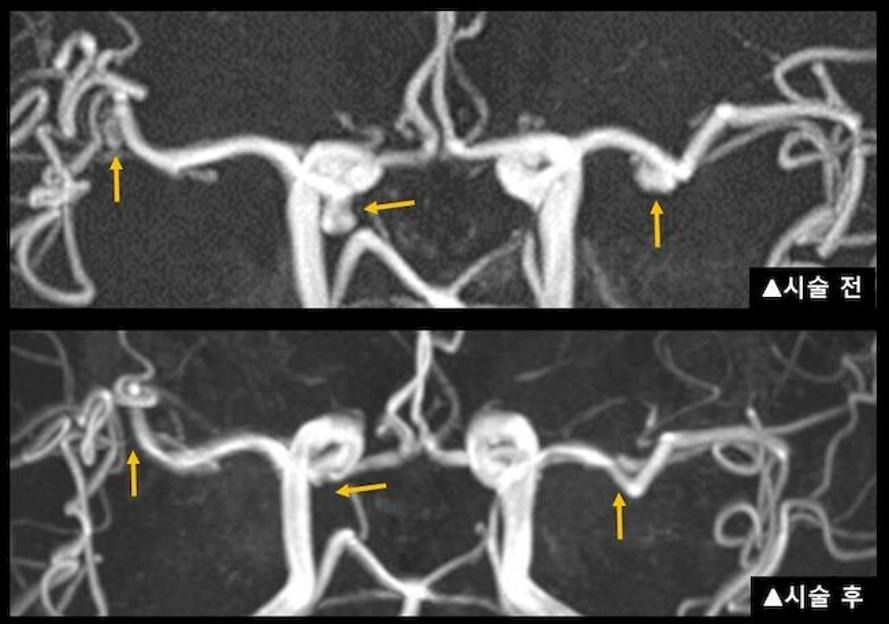

혈관 내 코일 색전술

이 방법은 허벅지나 손목의 동맥을 통해 카테터를 삽입하여 동맥류 내부에 백금 코일을 채워 혈류를 차단하는 최소 침습적 시술입니다. 이 시술은 개두술에 비해 회복이 빠르고 입원 기간이 짧습니다. 일반적으로 입원 기간은 2~4일이며, 시술 후 빠른 일상생활 복귀가 가능합니다. 그러나 재발 가능성이 있어 정기적인 추적 검사가 필요할 수 있습니다.

- 추적 관찰: 수술 후 정기적으로 병원을 방문하여 CT, MRI, 혈관 조영술 등을 통해 동맥류 상태와 재발 여부를 확인합니다. 코일 색전술을 받은 경우, 코일의 위치나 혈류 상태를 면밀히 관찰해야 합니다.